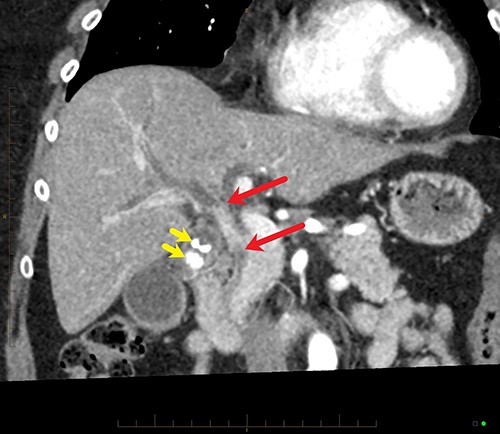

Coronal MPR of late arterial phase CT reveals segmental common hepatic duct stricture with circumferential wall thickening and enhancement (between red arrows) resulting in intrahepatic duct dilatation. Radiopaque calculi (yellow arrows) in the gallbladder.

Final histopathological assessment of the resected specimen reported a common bile duct adenocarcinoma (cholangiocarcinoma) measuring 37 mm in greatest dimension with extensive perineural, periductal, perinodal and peripancreatic soft tissue involvement. Metastatic carcinoma was found in 3/17 lymph nodes resected. The cholangiocarcinoma was staged as pT2N1M0. The gallbladder was found to have extensive high-grade biliary intraepithelial neoplasia with a primary gallbladder adenocarcinoma measuring 18 mm in greatest dimension entirely separate from the cholangiocarcinoma (Fig. 5). The patient recovered well from the procedure and was discharged home from hospital on post-operative Day 15. She has proceeded to have further treatment with adjuvant chemotherapy.